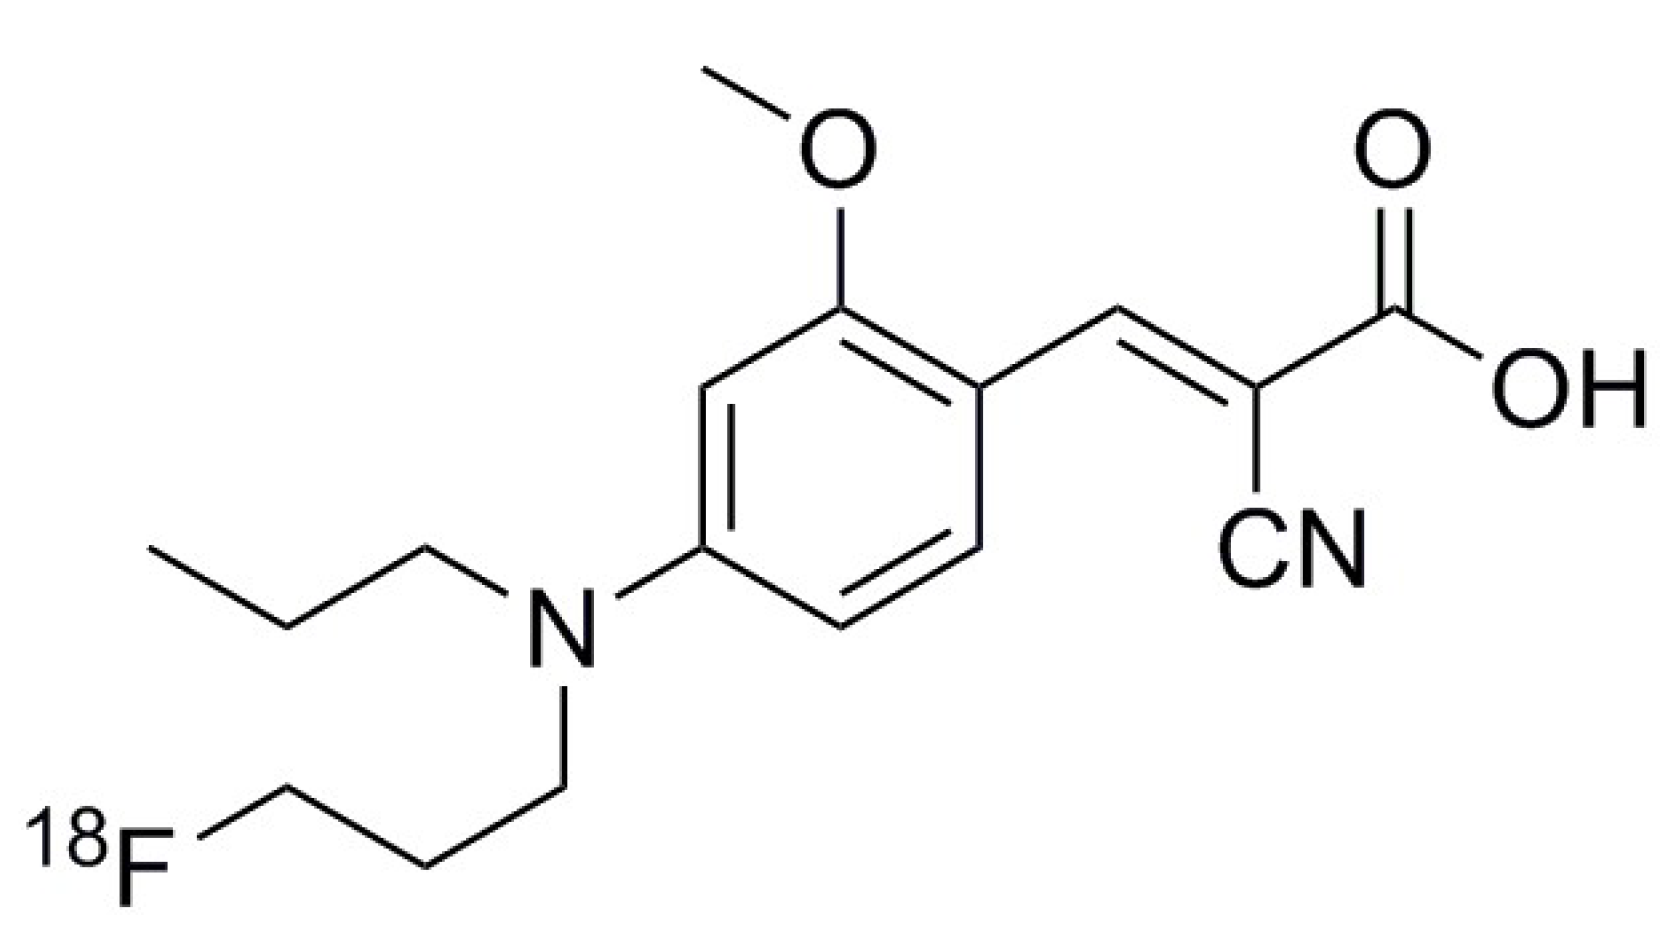

4.1. Synthesis of [18F]FACH

- Sadeghzadeh, M.; Moldovan, R.-P.; Fischer, S.; Wenzel, B.; Ludwig, F.-A.; Teodoro, R.; Deuther-Conrad, W.; Jonnalagadda, S.; Jonnalagadda, S.K.; Gudelis, E.; et al. Development and radiosynthesis of the first 18F-labeled inhibitor of monocarboxylate transporters (MCTs). J. Label. Comp. Radiopharm. 2019, 62, 411–424. [Google Scholar] [CrossRef] [PubMed]

- Sadeghzadeh, M.; Moldovan, R.-P.; Wenzel, B.; Kranz, M.; Deuther-Conrad, W.; Toussaint, M.; Fischer, S.; Ludwig, F.-A.; Teodoro, R.; Jonnalagadda, S.K.; et al. Development of the first 18F-labeled MCT1/MCT4 lactate transport inhibitor: Radiosynthesis and preliminary in vivo evaluation in mice. J. Label. Comp. Radiopharm. 2019, 62, S59–S60. [Google Scholar] [CrossRef] [PubMed]

- Sadeghzadeh, M.; Moldovan, R.-P.; Teodoro, R.; Brust, P.; Wenzel, B. One-step radiosynthesis of the MCTs imaging agent [18F]FACH by aliphatic 18F-labelling of a methylsulfonate precursor containing an unprotected carboxylic acid group. Sci. Rep. 2019, 9, 18890. [Google Scholar] [CrossRef] [PubMed]